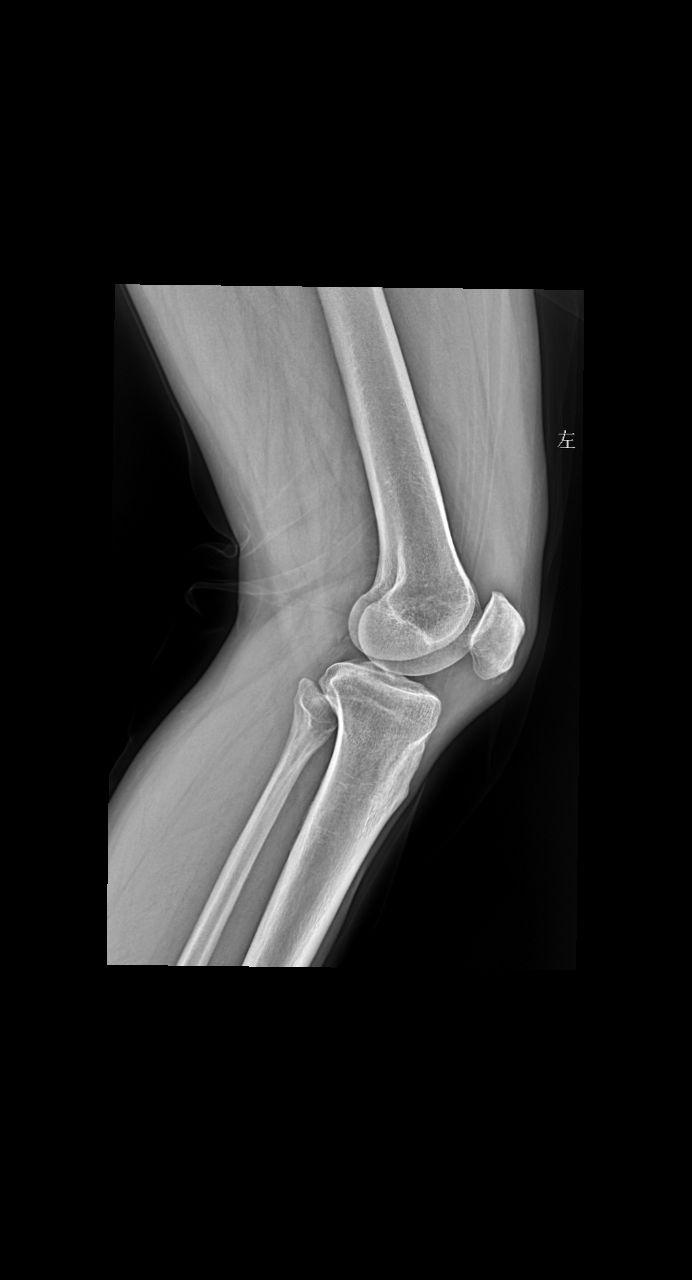

主诉 患者右侧膝盖疼痛 男47